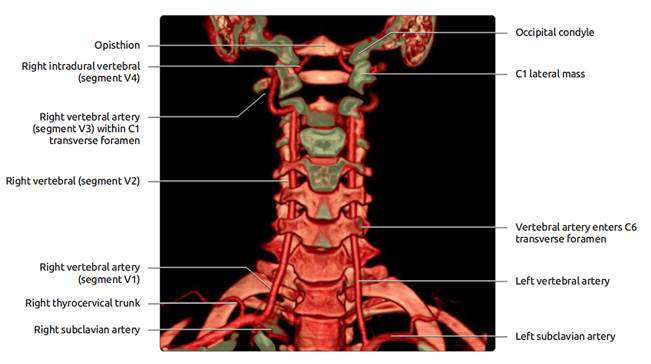

Extracranial vessels

Vertebral arteries

• V1 – origin (subclavan) to the point of entrance into

cervical tranverse process (usually C6)

• V2 – passes through tranverse processes to C2

• V3 – Exit at C2, laterally and posteriorly to pass

through transverse process of C1, the posteriomedial in a groove on the upper

surface of posterior arch of C1.

• V4 – Pierces dura and extends through foramen magnum –

up to basilar artery